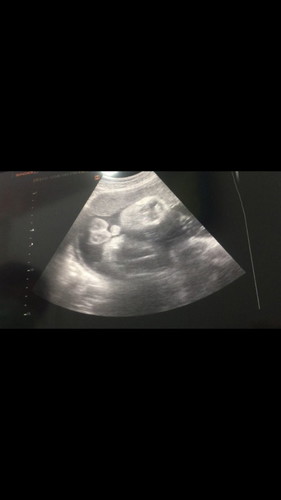

35+2 week ชายหรือหญิงค่ะ

ชายค่ะแม่ไข่สองใบชัดเจน😅

ไข่ชัดเจนค่ะแม่